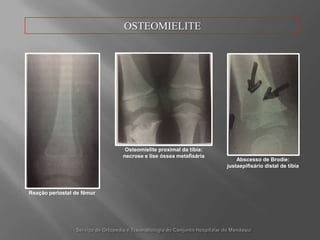

OSTEOMIELITEOsteomielite proximal datíbia: necrose e liseósseametafisáriaAbscesso de Brodie: justaepifisário distal de tíbiaReaçãoperiostal de fêmurServiço de Ortopedia e Traumatologia do ConjuntoHospitalar do Mandaqui